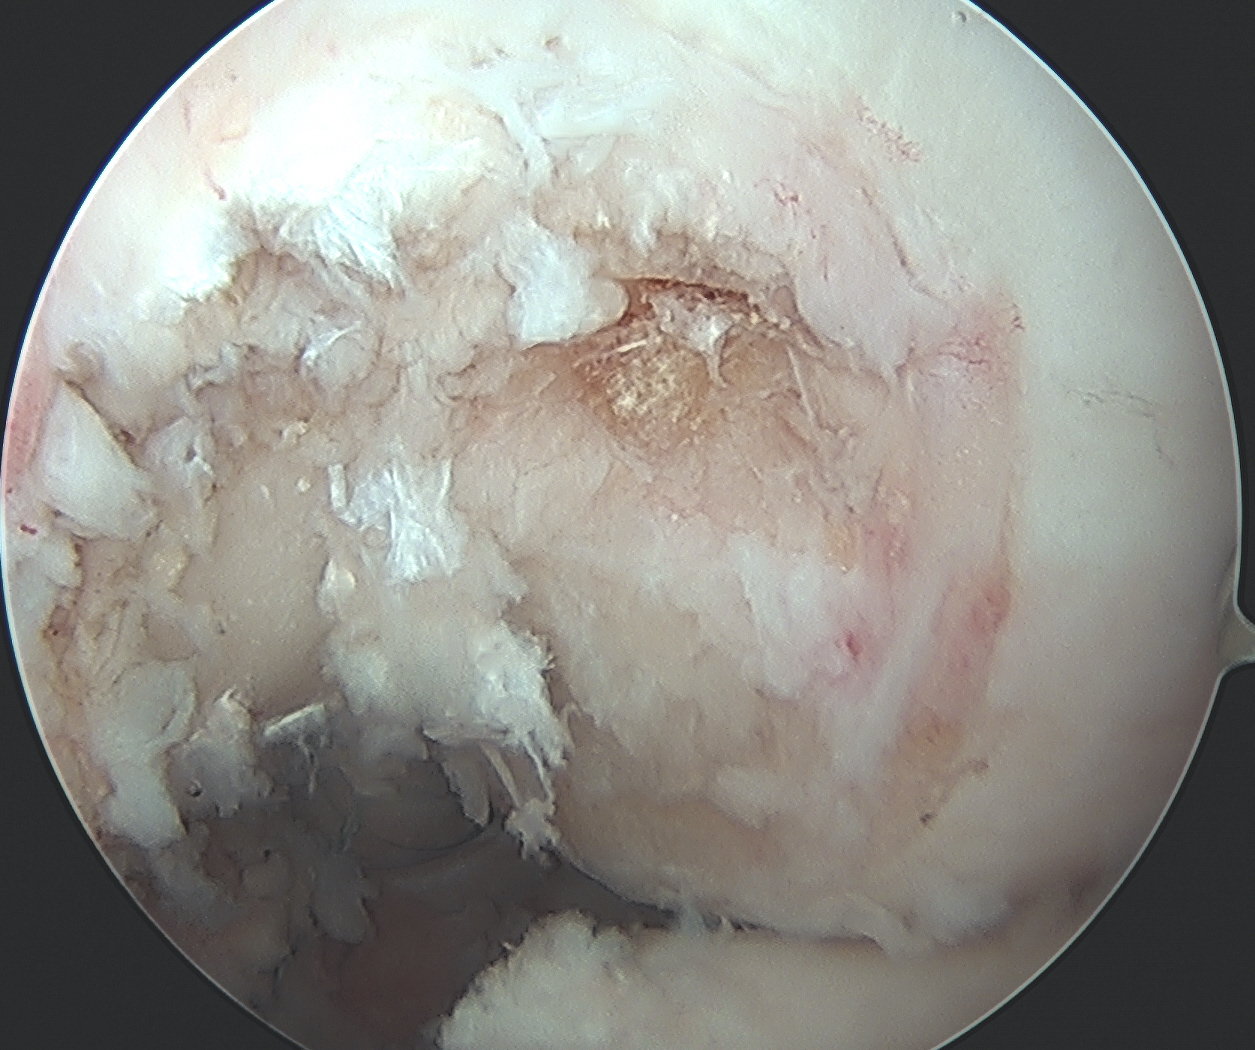

PCL facet 1PCL tibial tunnel

PCL tibial facet                                                           Tibial tunnel beath pin

Clear tibial origin

Need adequate visualisation of the PCL facet

- down at least 1 - 2 cm below articular surface

- combination of shaver and electrocautery

- usually need to release some of the capsular insertion onto posterior tibia